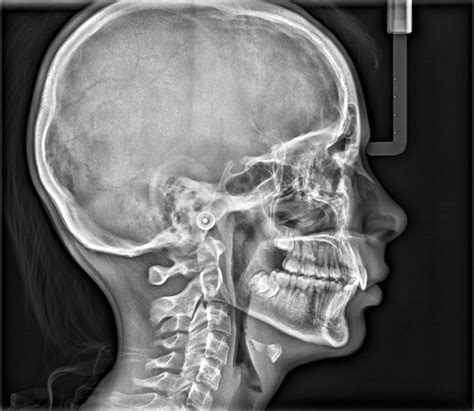

A Cephalometric X Ray is a specialized type of radiograph used to analyze the relationship between the teeth and the jaw. It provides a two-dimensional view of the skull, focusing on the facial bones and teeth. This imaging technique is invaluable for diagnosing and treating various orthodontic conditions, including malocclusions, jaw discrepancies, and facial asymmetries.

The patient’s head is positioned so that the Frankfort plane (a line drawn from the top of the ear canal to the bottom of the eye socket) is parallel to the floor. This ensures that the X-ray beam passes through the skull at the correct angle, providing an accurate image of the facial bones and teeth.

The X-ray machine is then activated, and a beam of radiation is directed through the patient’s head. The radiation passes through the soft tissues and is absorbed by the denser bone structures, creating a detailed image on the X-ray film or digital sensor.

Once the X-ray is taken, the image is developed. In traditional film-based systems, the film is processed in a darkroom. In digital systems, the image is instantly available on a computer screen. The orthodontist then reviews the image to assess the patient’s dental and skeletal structures.